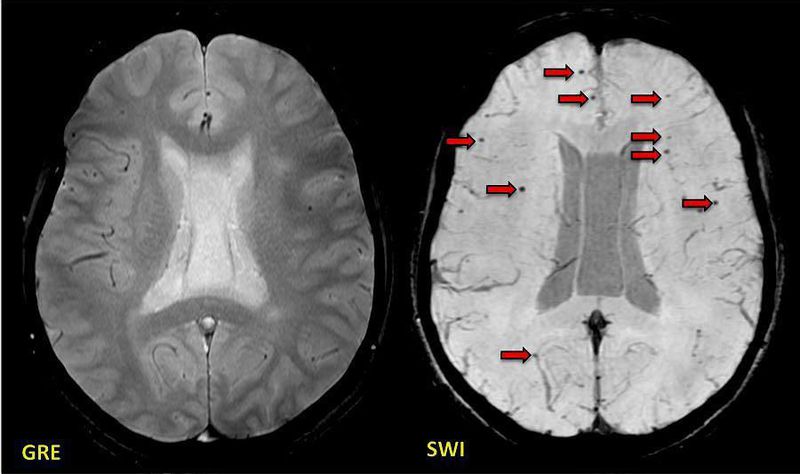

Post-traumatic brain injury showing many more axonal microhemorrhages (arrows) on SWI than on GRE